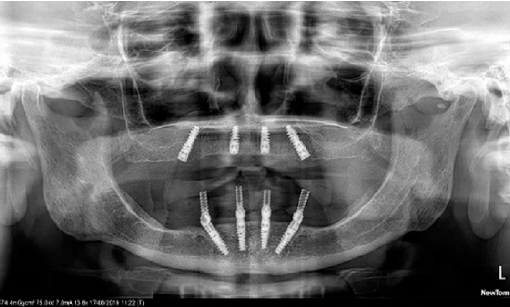

Se extrajeron los dientes remanentes y se colocaron las prótesis inmediatas. Después de seis meses de la maduración del hueso, se elaboraron las guías quirúrgicas permisivas del maxilar y la mandíbula. Se le aplicó anestesia local con vasoconstrictor (Medicaine 1/100,000 (articaine-epinephrine), Septodont Holding, Saint-Maur-des-Fossés, Francia) en ambas arcadas, se hizo una meseta en la parte anterior de la mandíbula para que los implantes queden a la misma altura en el reborde alveolar, y se siguió el protocolo de cirugía del fabricante de implantes (Nobel Active® RP, Nobel Biocare Services AG, Kloten, Suiza), cuatro en cada arcada: dos anteriores rectos y dos posteriores inclinados21,22. Los implantes mandibulares recibieron pilares transmucosos (Multi-unit abutment, Nobel Biocare Services AG, Kloten, Suiza): 2 anteriores rectos y 2 posteriores de 17° con un torque de 35 Newtons para corregir la angulación de los implantes y hacer la conversión de la dentadura inmediata a una prótesis total fija atornillada. A los dos meses de la cirugía, se colocaron los pilares transmucosos del maxilar: 2 anteriores rectos y 2 posteriores de 17° (Figura 2).

Figura 2 Ortopantomografía de los implantes dentales nobel en ambas arcadas, con transmucosos (multiunits; nobel biocare) en mandíbula.